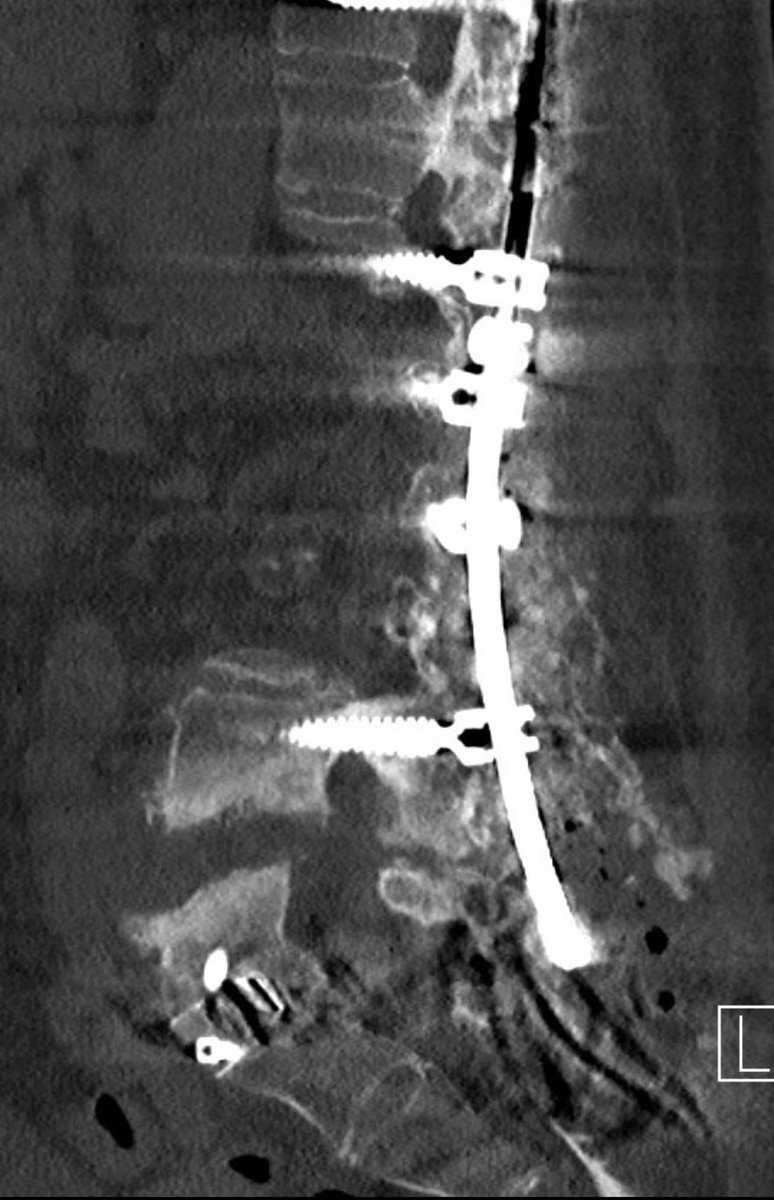

Excited to be featured on this Neuro Pathways Podcast episode discussing diagnosis and intervention of idiopathic scoliosis! #scoliosis #spinesurgery @CleClinicNS @ClevelandClinic podcasts.apple.com/us/podcast/neu…

ABNS Board Certified Neurosurgeon, Assistant Professor CWRU. Complex Spine Deformity, Spine Oncology, Scoliosis. Follower of Christ. Tweets are my own.